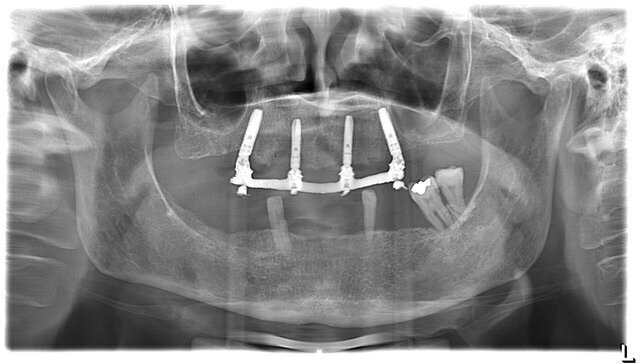

La paziente A. S. di anni 67 si presentata in visita richiedendo la sostituzione della protesi totale superiore con una nuova protesi, possibilmente fissa (Figg. 1-3). Essendo l’anamnesi negativa si è proceduto allo studio e alla pianificazione del caso. La paziente si è presentata con una OPT delle arcate dentarie (Fig. 4) che evidenziava un’ottima quantità di osso alveolare residuo. Dopo esame intra- orale si prescrive una CBCT per poter pianificare nel dettaglio la chirurgia implantare.

La nuova protesi totale provvisoria ha portato immediatamente un miglioramento funzionale ed estetico, con un notevole beneficio psicologico sulla paziente ed un enorme vantaggio per il prosieguo della terapia (Figg. 8-10). Il nuovo montaggio con denti di maggiori dimensioni ed una differente occlusione ha conferito un miglior supporto al labbro superiore ed una migliorata estetica del sorriso (Fig. 11). Alla luce della nuova situazione, accettata e gradita dalla paziente, si è incominciato a pianificare la procedura chirurgica. Avendo la CBCT evidenziato dei volumi ossei adeguati (Fig. 12), si è proceduto allo studio del caso mediante un software di chirurgia guidata (Simplant, Dentsply-Sirona) (Figg. 13, 14).

Verificata la precisione del lavoro si procede alla consegna. La Fig. 38 evidenzia la perfetta salute dei tessuti peri-implantari a protezione dei MUA, e nelle figure 39 e 40 evidenziano l’ottimo adattamento del manufatto finale ai tessuti intra ed extra-orali. La panoramica di controllo a 12 mesi dal completamento del lavoro evidenzia una perfetta stabilità dei livelli ossei dopo il carico protesico (Fig. 41).